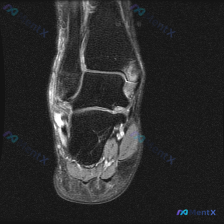

看到一个很典型的足部MRI读片病例,整理了影像特征和完整的分析思路,分享给大家一起讨论。 一、病例影像基本信息 这是一张足部冠状位液体敏感序列(T2-FS/STIR)MRI,图像对比度良好,无明显伪影,主要显示后足跟骨、距骨及踝关节周边软组织。 二、核心影像发现 1. 骨骼:跟骨信号均匀,未见皮质中...

病例影像分析分享 今天整理了一例踝关节MRI的分析思路,原始提示看到「软组织积液」,我们一步步来拆解: 病例影像基本信息 这是一例踝关节MRI冠状位T2加权像,我们先做系统性解剖评估: 1. 骨与关节:胫距关节、距下关节间隙正常,关节面平滑,胫骨远端、距骨、跟骨骨髓信号均匀,没有骨赘、软骨下囊肿、骨...